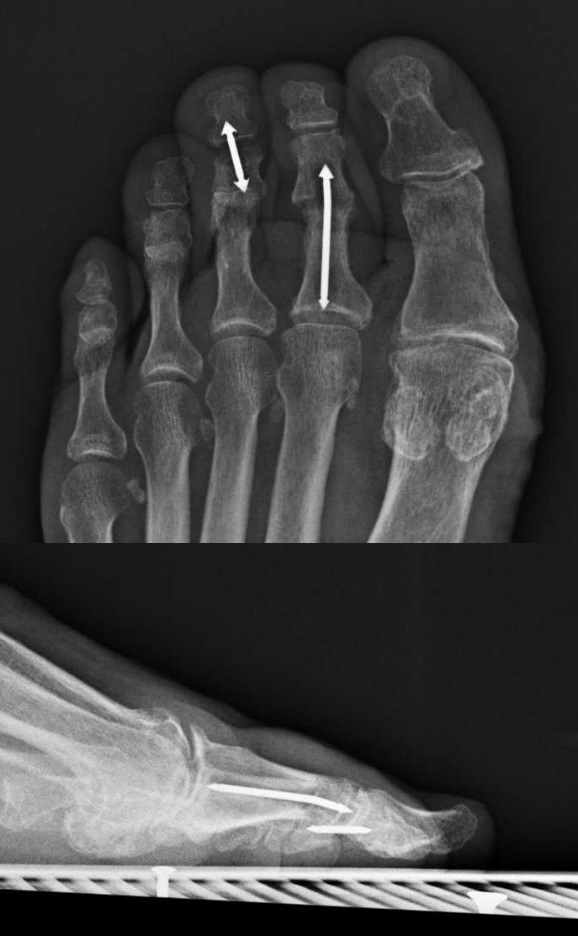

Figure 1 from Hammertoe Correction With KWire Fixation Semantic Scholar Hammer Toe Wire Removal The hammertoe can be flexible or. the main goal of hammertoe surgery is to correct the deformity, which will relieve the pain. types of surgery. A hammer toe is a potentially painful deformity of the. hammer toe is a condition that affects one of the three middle toes, causing the toe to bend upward at its middle. Hammer Toe Wire Removal.